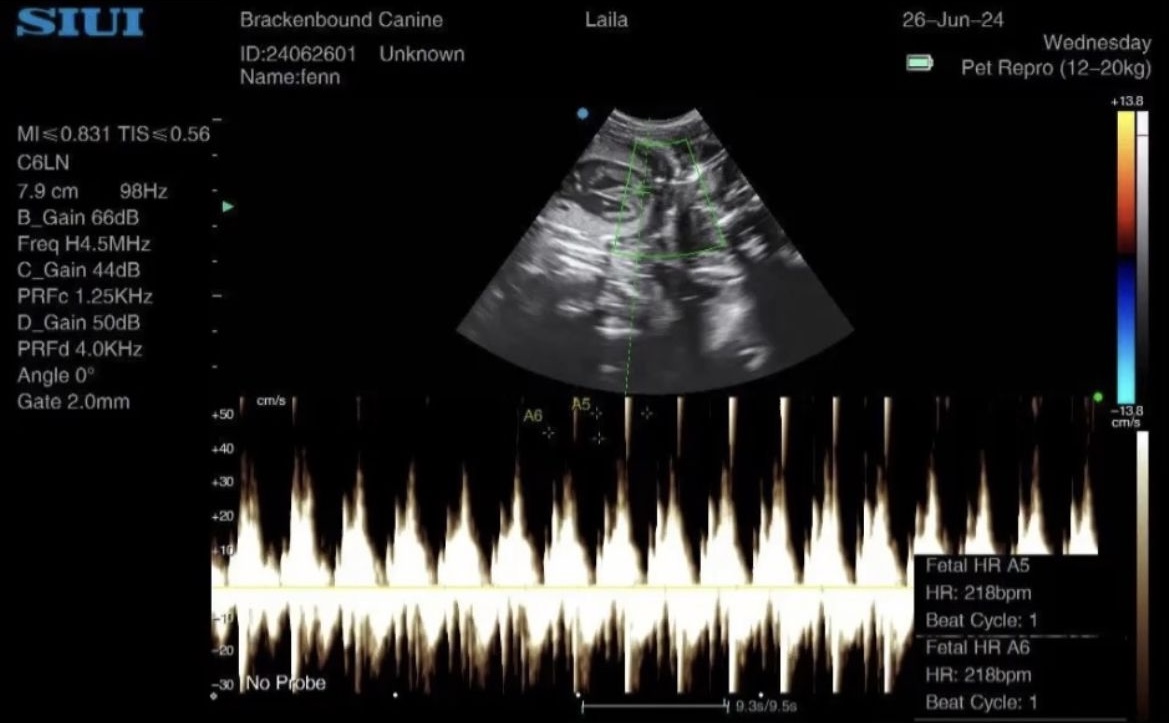

Following miscarriage of her entire litter, Fenn’s owner was understandably nervous during her subsequent pregnancy so we paid extra attention to Fenn throughout. This was a reassurance scan at full

Gestational sac measurements for working Labrador Fenn. This was a sad case actually. All seemed to be going well but Fenn was part of a fairly large house move and